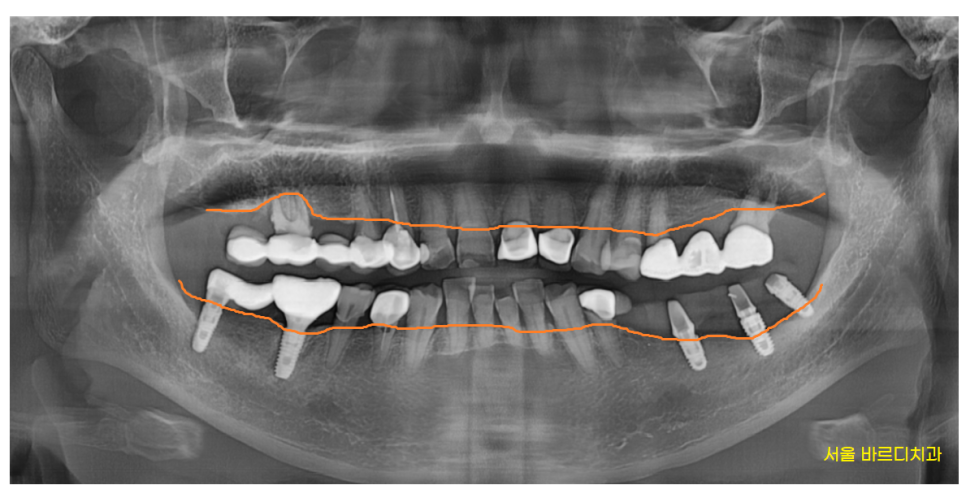

망월동 치과에서는

문제가 되는 치아들을 진단해드렸습니다.

이해하기 쉽도록

보통 이렇게 그림을 그려 말씀드립니다.

한곳이 아닌

여러곳을 치료해야할 때는

치료 순서를 정하게 되는데요.